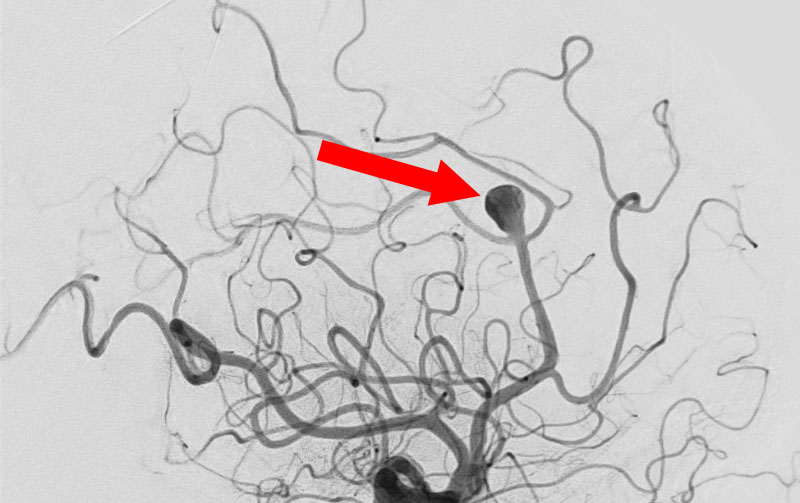

'25年11月

左内頚動脈脳動脈瘤

60代

大阪府の病院

No.1595 手術前